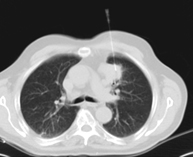

- TC Tòrax

Prova diagnòstica que consisteix en obtenir imatges del tòrax d'alta definició anatòmica (pulmons, cor, mediastí, grans vasos, caixa toràcica, etc. ) mitjançant l'ús d'un equip de TC (Tomografia Computeritzada). Aquestes imatges s'estudien posteriorment en una estació de treball que permet reconstruccions bidimensionals en diferents plànols de l'espai i també reconstruccions 3D (volumètriques). Alguns estudis requereixen l'ús de contrast iodat per millorar la definició de les imatges. - Angio –TC Aorta toràcica